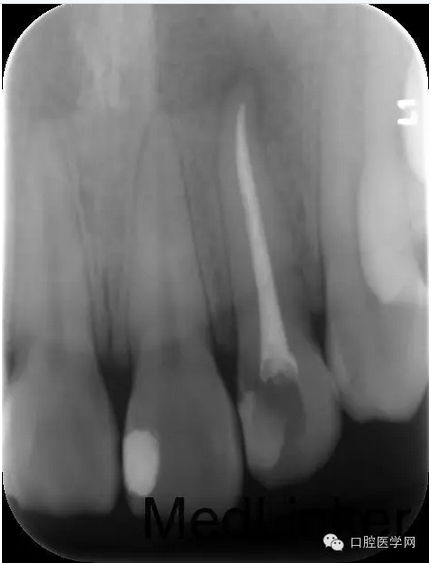

第三次:復診無不適。叩診無不適,無松動。處置:去除暫封物,鹽水沖洗,試尖,牙膠尖+AHplus糊劑冷測壓充填,玻璃離子體充填。

第四次:復診無不適。叩診無不適,無松動。復查X線片,根尖密度減低區(qū)明顯減小,玻璃離子體部分去除,樹脂充填,調(diào)牙合,拋光。醫(yī)囑待18周歲后行冠永久修復。